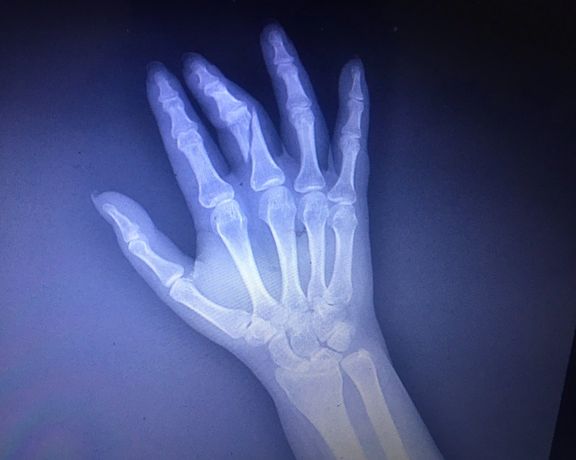

گزارشگران بدون مرز حمله مامور حراست به فائزه مومنی، خبرنگار را که باعث شکستن دست او شد، محکوم کرد. مومنی در پی مراجعه به مجموعه ساعی برای تهیه گزارش درباره واکسیناسیون کرونا، از سوی حراست مجموعه مورد ضرب و شتم قرار گرفت